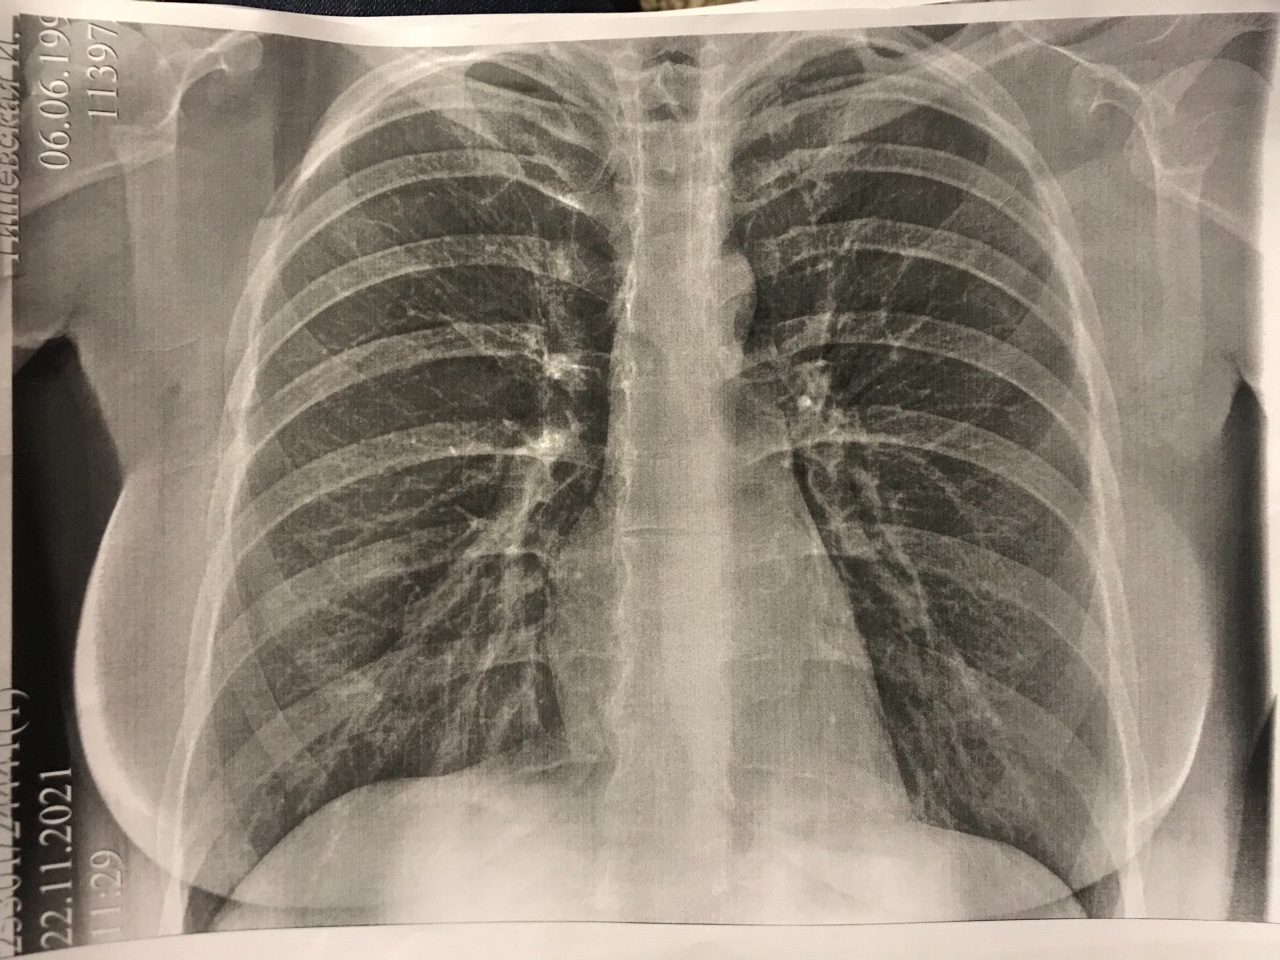

Медицина и диагностика: Аномалии ребер на рентгене